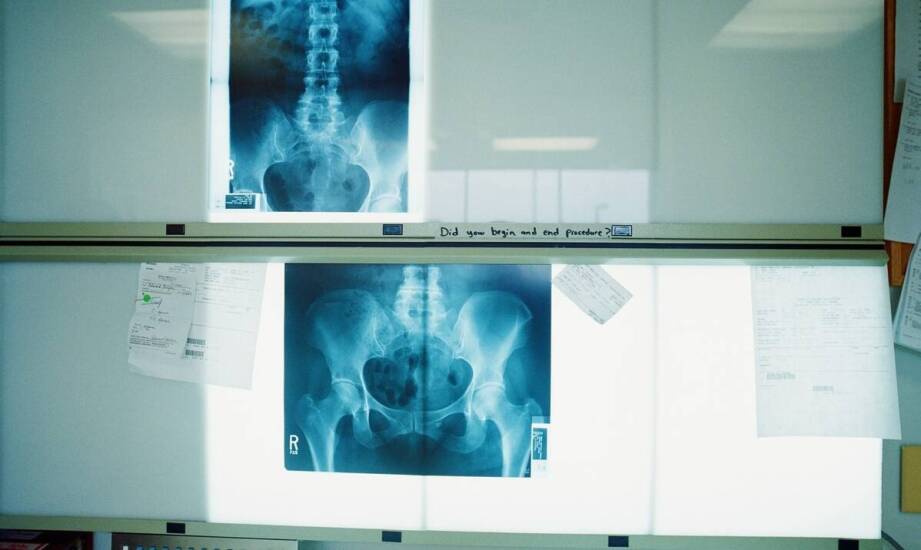

Nowoczesne technologie w diagnostyce RTG odgrywają kluczową rolę w poprawie jakości obrazowania oraz precyzji diagnozowania schorzeń. Zaawansowane funkcje programów do zdjęć RTG znacząco wpływają na dokładność analizowanych obrazów, co pozwala lekarzom na szybsze i trafniejsze postawienie diagnozy. Innowacje w tych rozwiązaniach mogą zrewolucjonizować podejście do analizy obrazów, przynosząc korzyści zarówno pacjentom, jak i specjalistom medycznym.

Zaawansowane oprogramowanie do zdjęć RTG oferuje programy, które znacząco wpływają na precyzję diagnostyki. Automatyczne rozpoznawanie wzorców umożliwia szybsze i dokładniejsze identyfikowanie nieprawidłowości, co przekłada się na lepszą jakość diagnoz. Innowacyjny program do zdjęć rtg pozwala lekarzom dostrzegać subtelne detale, które mogą być kluczowe dla postawienia właściwej diagnozy. Integracja z systemami zarządzania danymi ułatwia dostęp do informacji oraz ich analizę, co zwiększa efektywność pracy personelu medycznego. W praktyce klinicznej zaawansowane funkcje tego oprogramowania przekładają się na wyższą jakość usług medycznych oraz lepsze wyniki leczenia pacjentów. Przykłady zastosowań pokazują, jak innowacyjne rozwiązania od MP2 mogą wspierać pracę specjalistów oraz poprawiać dokładność diagnozowania w różnych dziedzinach medycyny, w tym w diagnostyce obrazowej.

Zaawansowane algorytmy analizy obrazów odgrywają kluczową rolę w procesie diagnostycznym, wspierając radiologów w identyfikacji patologii. Sztuczna inteligencja oraz uczenie maszynowe umożliwiają analizowanie zdjęć RTG z większą precyzją, co zwiększa pewność diagnoz. Przykłady badań pokazują skuteczność tych technologii w wykrywaniu chorób. Algorytmy te potrafią rozpoznawać wzorce i anomalia, które mogą umknąć uwadze ludzkiego oka. Dzięki temu lekarze mają możliwość podejmowania lepszych decyzji diagnostycznych i terapeutycznych. Współpraca z zespołem specjalistów oraz inwestycje w nowoczesne technologie są niezbędne dla dalszego rozwoju tej dziedziny. Wprowadzenie zaawansowanych funkcji programów do zdjęć RTG pozytywnie wpływa na precyzję diagnostyki, co przekłada się na wyższą jakość opieki zdrowotnej oraz satysfakcję pacjentów i lekarzy.